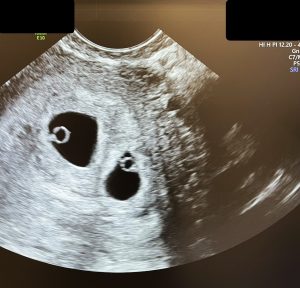

Zis și făcut: i-am rugat să completeze în plus, pe consimțământul informat, o frază prin care recunoșteau că li s-au explicat riscurile suplimentare și consecințele transferului de 2 embrioni și că și le asumă, și am transferat cei 2 embrioni. Iar peste 3 săptămâni am confirmat la ecografie sarcina gemelară.😊😬